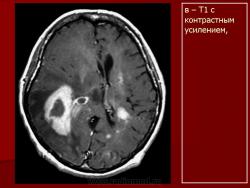

Лимфомы головного мозга.